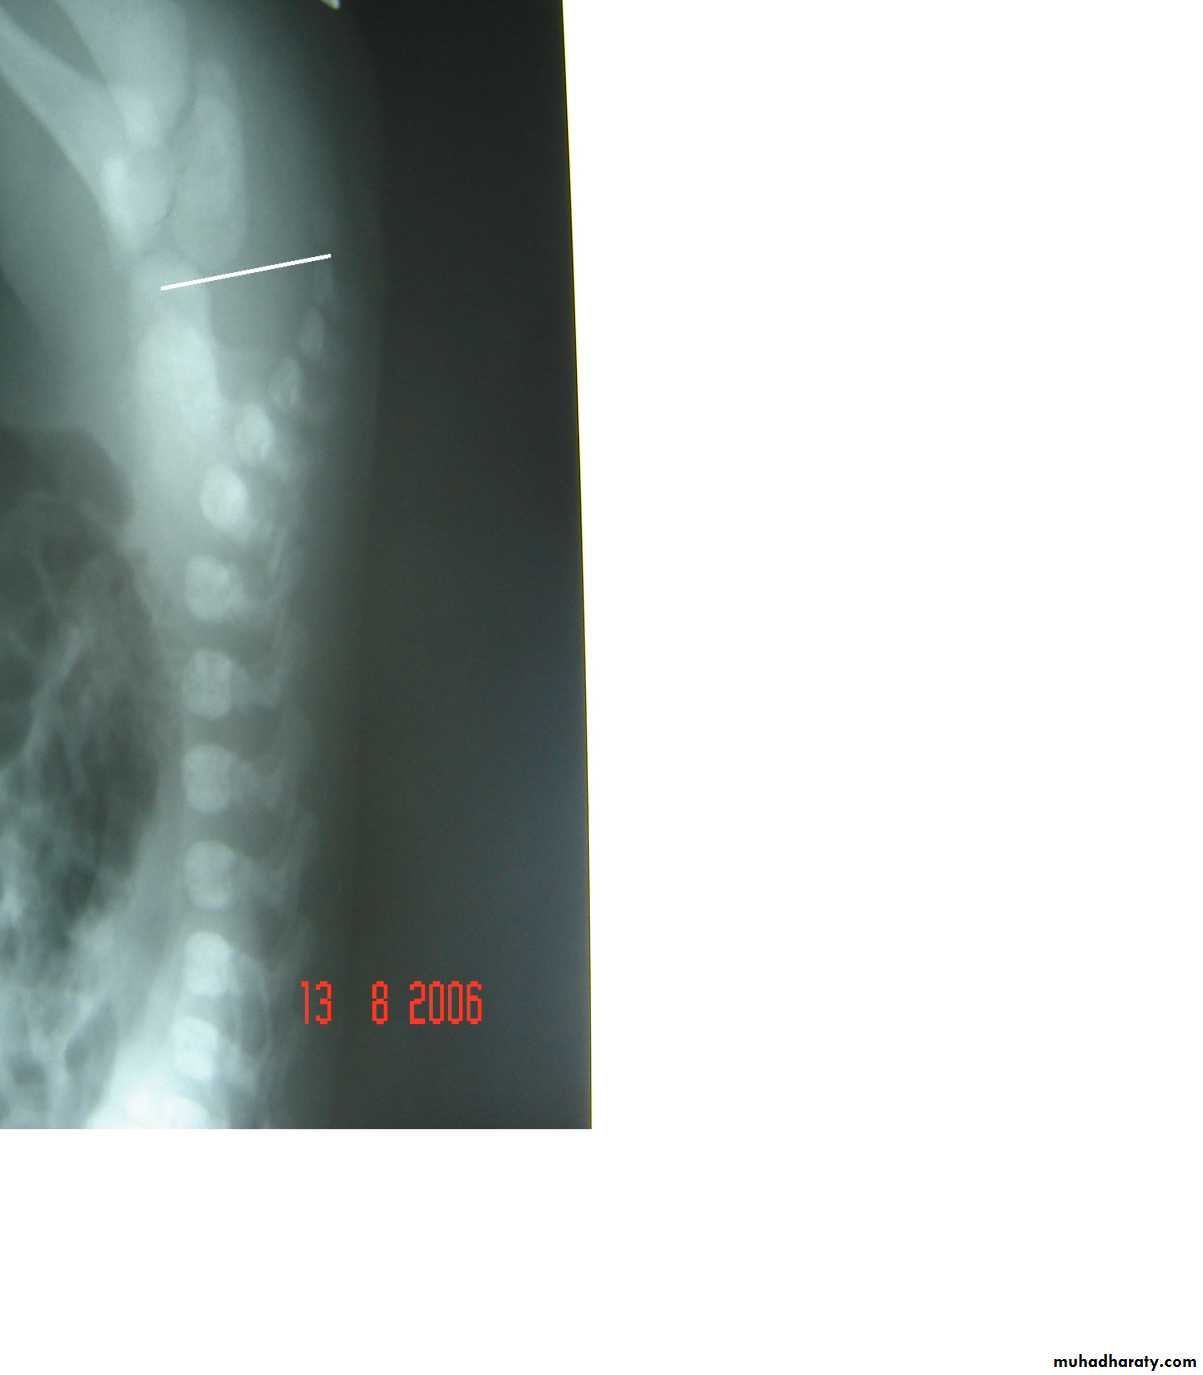

Hirschprungs disease